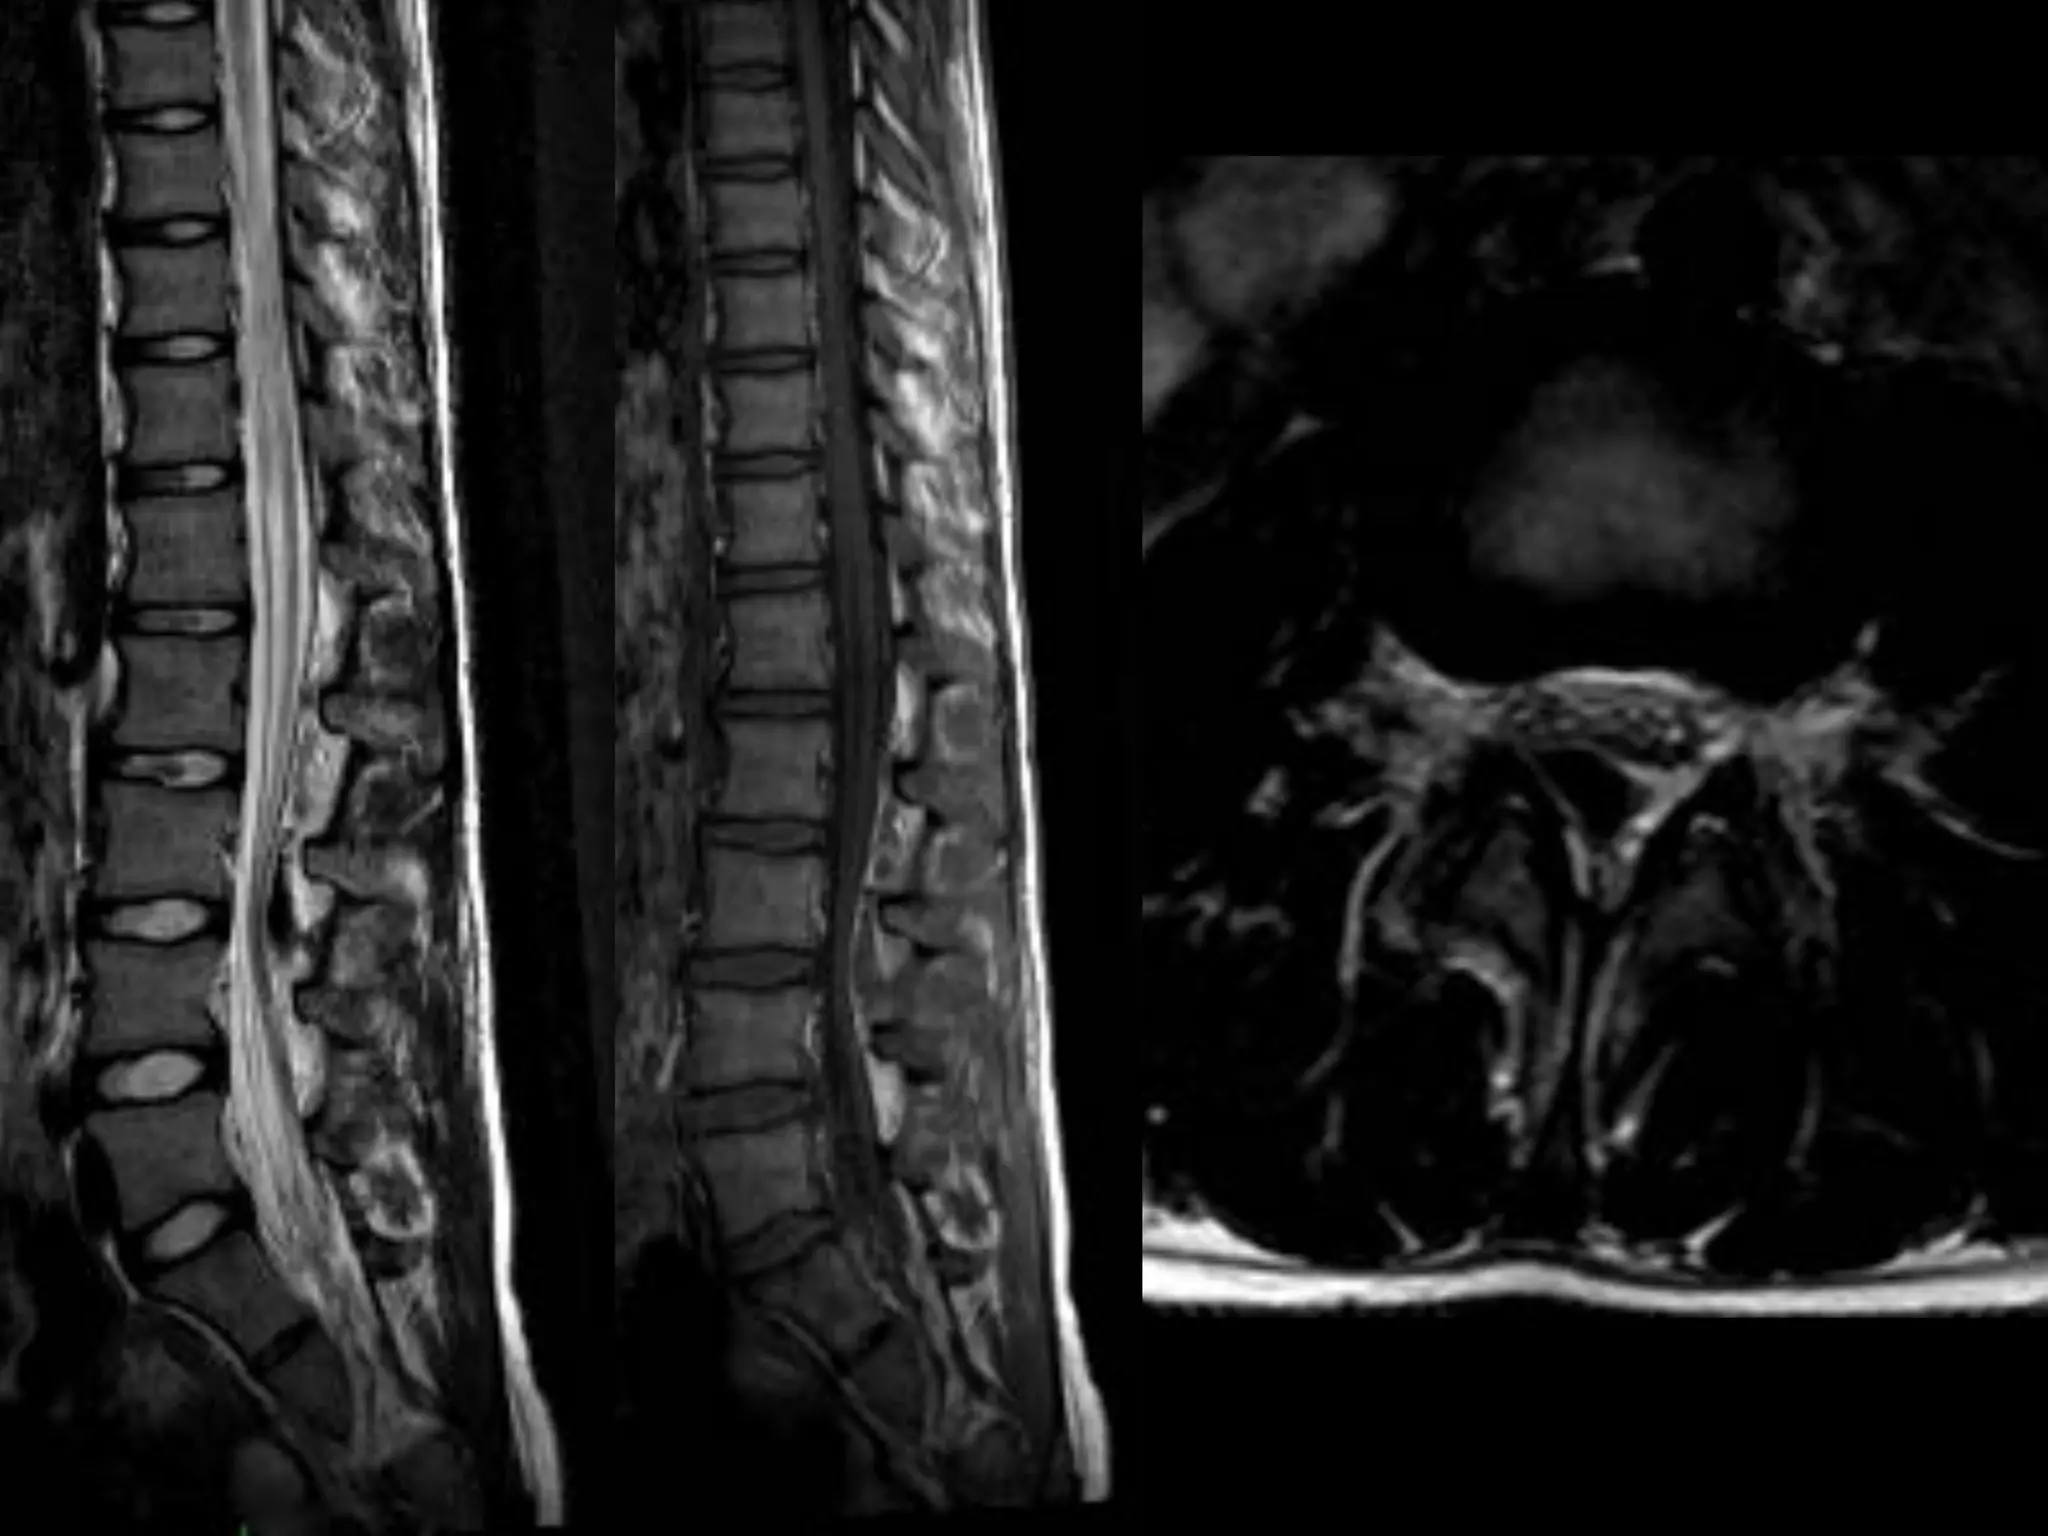

Spinal cord MRI

Causative investigation

Meningeal diverticula . ..

Level of leakage

Congestion of venous plexuses

Fluid collection in the epidural space

Collapsing of dural sac